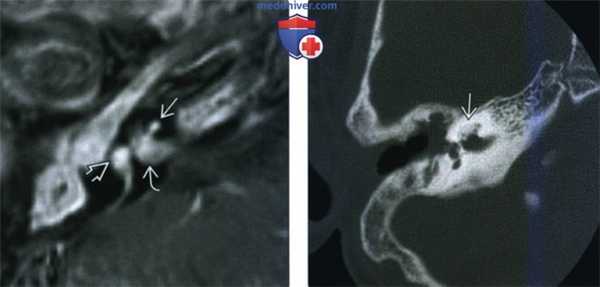

(Слева) При аксиальной КТ правой височной кости у пациента с правосторонней НСТУ, которому ранее была выполнена мастоидэктомия, определяется выраженное утолщение стержня улитки (постоперационный ОЛ).

(Справа) При сагиттальной МРТ Т2 ВИ на уровне наружного слухового канала у пациента с тяжелым ипсилатеральным ОЛ улитки определяется выраженная атрофия улиткового нерва по сравнению с нормальными лицевым и вестибулярными нервами - типичная сопутствующая находка при тяжелом ОЛ.